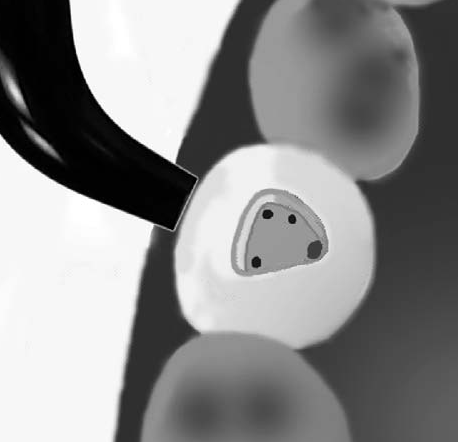

Como método para ubicar los orificios de entrada de los conductos solemos utilizar la transiluminación dentaria.

El conducto y el orificio es esencialmente un agujero en la raíz, la transmisión de luz  muestra al orificio de entrada del conducto como una mancha oscura en un fondo brillante. Ver imagen izquierda superior, la siguiente imagen es el resultado de utilizar una cámara intraoral, con 10 aumentos (X10)

En la imagen derecha se observa el dispositivo de transiluminación dentaria

DS: dentina secundaria de color más claro. Cámara intraoral X10 aumentos.